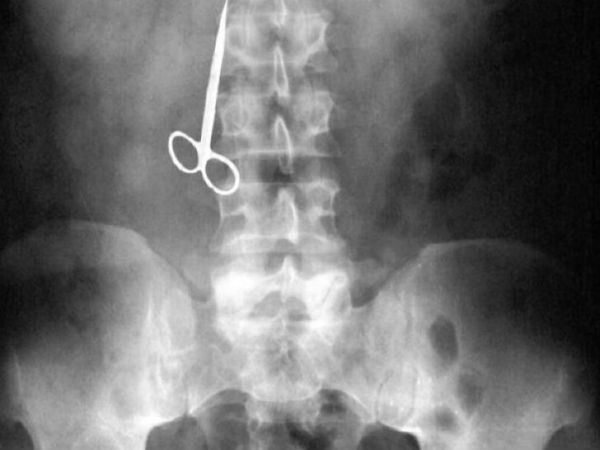

Одна женщина не нашла дома зубочисток после обеда и решила использовать ножницы.